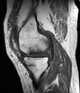

Osteonecrosis of the medial tibial condyle

Spontaneous osteonecrosis of the Knee, is the result of vascular arterial insufficiency to the medial femoral condyle of the knee resulting in necrosis and destruction of bone. It is often unilateral and can be associated with a meniscal tear. [Source: Wikipedia ]